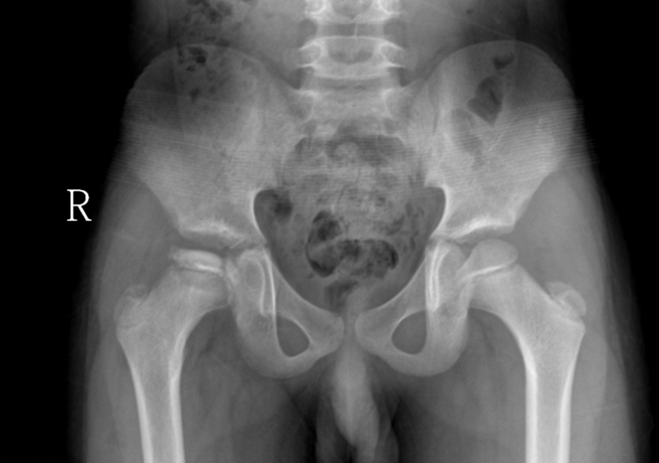

Trẻ thường đến khám với  đi khập khiểng không đau khoảng 1-3 tháng. Đau có thể xuất hiện ở khớp gối, khớp háng hoặc đùi làm cho trẻ hạn chế các hoạt động thường ngày. Khám thực thể thấy giảm độ xoay trong và dạng háng. Teo các cơ đùi, cơ mông cũng như ngắn chi trong trường hợp muộn. Khi nghi ngờ trẻ bị bệnh Legg – Calve – Perthes, X quang khung chậu thẳng và tư thế chân ếch (Lauenstein views) được chỉ định. Trên phim x quang có thể thấy hình ảnh dãn rộng khe khớp, chỏm xương đùi nhỏ và đặc hơn, gãy xương dưới sụn; ở giai đoạn sau có thể thấy chỏm bị dẹt, phân mảnh hoặc hồi phục trở lại. Tuy nhiên trong giai đoạn sớm, x quang thường không phát hiện được tổn thương, phải nhờ đến chụp cộng hưởng từ (MRI) hoặc bone scans.

Hình ảnh chỏm xương đùi phải biến dạng, tăng mật độ do hoại tử vô mạch

(Nguồn: BVĐK tỉnh Quảng Trị)